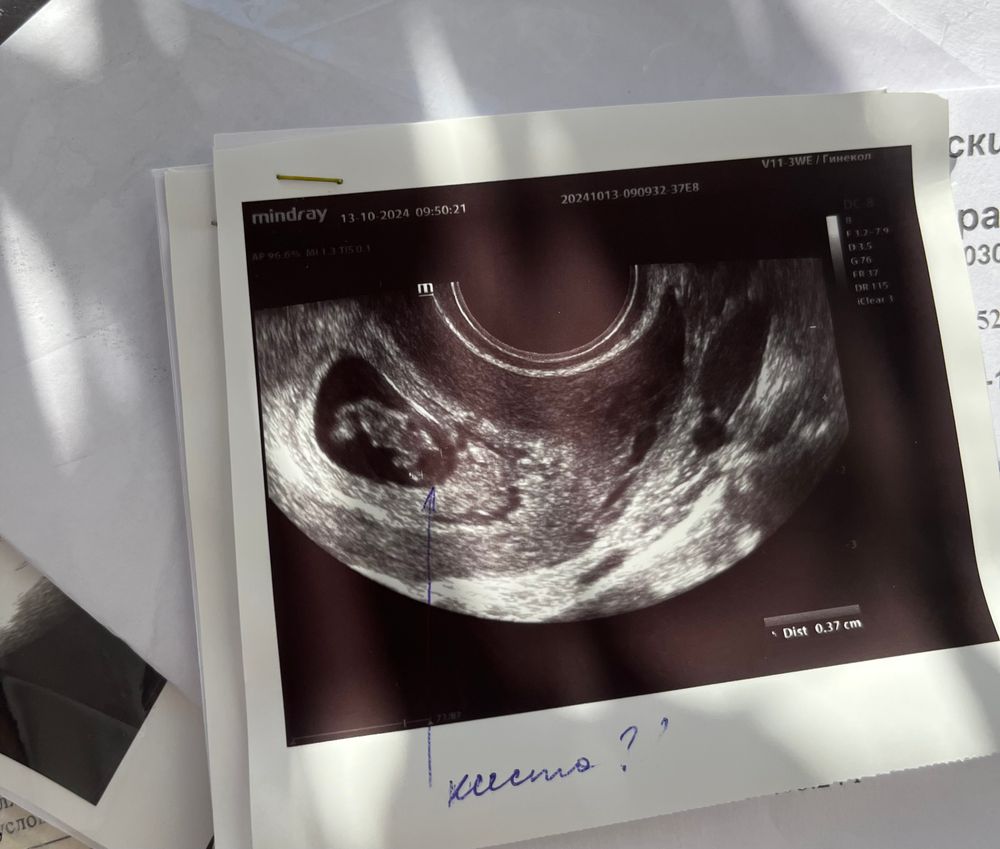

Киста в голове у плода на 7-8 неделе беременности

Здравствуйте как у вас дела? Мне тоже самое врач сказала, что у плода киста в головном мозге, срок 8 недель

Может это не в голове? Он же еще маленький очень, какая киста на таком сроке. Странно, ну вы не накручиваете себя. Узисты разные бывают и аппараты разные. Эти картинки черно-белые надо грамотно расшифровывать.

У нас была, правда называли это псевдокистами. Обнаружили только на втором скрининге, даже не уверена видно ли что-то подобное на таком маленьком сроке. Вообще, это считается маркером хромосомных аномалий, но если кроме кист больше ничего нет, то на это даже внимания не обращают, само по себе это не значит абсолютно ничего, есть и все. То есть эти кисты, в случае ха, идут бонусом к чему-то К 25 неделе они рассосались и мы про них забыли

Алёна, ну знаете, такие кисты не появляются позже, их находят позже и видят где-то на втором скрининге. Появляются они при закладке головного мозга, то есть вот только сейчас у вас. Чето я сильно сомневаюсь, что на 7 неделях там реально что-то увидеть, не загоняйтесь, на первом скрининге будет все понятно. У меня тоже предыдущая беременность была неудачная, причина скорее всего тоже в за, в последнюю я сильно переболела ОРВИ (была все время на ногах, старший ребенок тоже болел, приходилось на руках его носить много через усталость) на ранних сроках, мне сказали, что из-за этого, при закладке мозга, у ребенка появились кисты в голове. На первом скрининге ничего такого видно не было

У нас были кисты сосудистых сплетений головного мозга. Если сплетений, то это не страшно, много у кого бывает. Проходит к 3 скринингу обычно. Да и многие кисты сами рассасываются до рождения. Но на консультацию к генетику обязательно сходите

Ксения Виноградова, просто меня насторожило именно то, что это на таком маленьком сроке ☹️ По крайней мере в интернете пишут, что такие вот образования обычно на более позднем сроке появляются, как я поняла ☹️ Да, к генетику схожу обязательно 🙏🏽